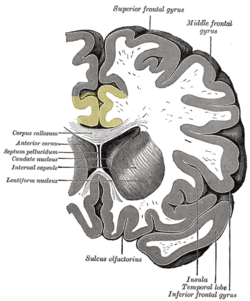

![]() Medial surface of left cerebral hemisphere, with cingulate gyrus and cingulate sulcus highlighted. | |

The cingulate cortex, a part of the limbic cortex, is a part of the brain situated in the medial aspect of the cerebral cortex. The cingulate cortex includes the entire cingulate gyrus, which lies immediately above the corpus callosum, and the continuation of this in the cingulate sulcus. The cingulate cortex is usually considered part of the limbic lobe.

Based on cerebral cytoarchitectonics it has been divided into the Brodmann areas 23, 24, 26, 29, 30, 31, 32 and 33. The areas 26, 29 and 30 are usually referred to as the retrosplenial areas.